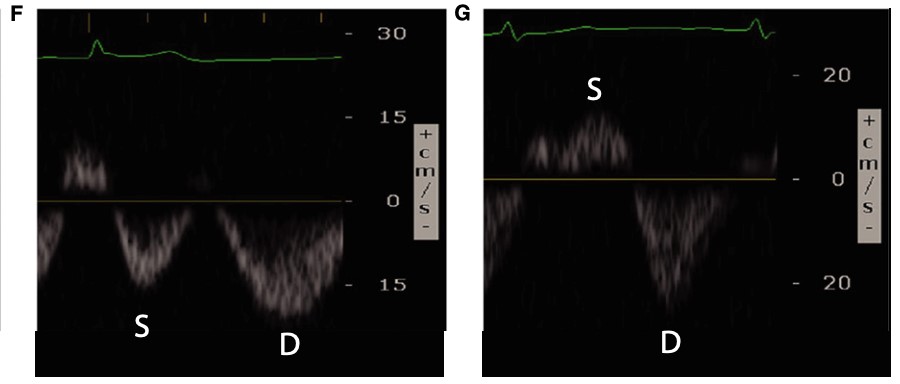

Conversely, renal venous flow remains a more specific marker for renal vein congestion and renosarca as it allows us to assess venous congestion within the venous system itself. As right atrial pressures increase, similar in nature to the hepatic vein, the normal continuous intra-renal venous doppler pattern (Figure 5) transitions to an interrupted biphasic pattern (Figure 8A), and ultimately to a primarily diastolic venous flow pattern (Figure 8B). This remains physiologically similar to our understanding of the hepatic venous waveforms: as right atrial pressures rise; the systolic venous flow will gradually decrease until a primary diastolic venous flow is present. At this point, the venous system loses its ability to compensate for increased fluid. When compared to hepatic venous flow, renal flow provides two major advantages: an ability to easily determine systolic and diastolic flow and being more specific to renal venous congestion.

Figure 8. Abnormal renal vein Doppler6

(Reproduced with permission)

A: Biphasic systolic and diastolic venous flow

B: Monophasic diastolic venous flow